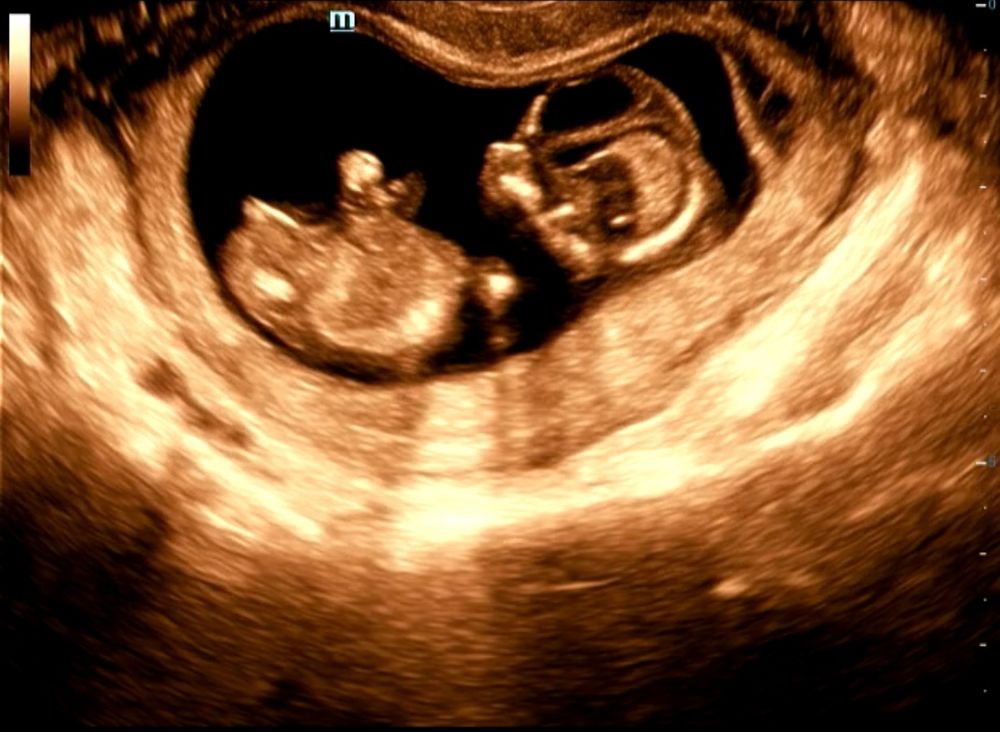

Как думаете кто по УЗИ? Первый скрининг.

Мне кажется девочка) В 11 недель у сына было примерно как у Вас на узи, а в 13 недель уже поднялся бугорок Изображение

Женя, вот как раз и пыталась разглядеть половой бугорок))) но не уверена, что это именно оно, а не часть ноги так засветилась или пуповина, срок здесь 12 и 1